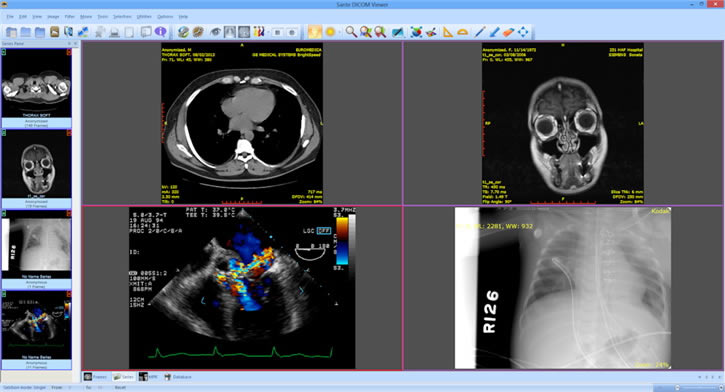

Sante DICOM中文版是一款用于医疗领域的办公软件,这款软件用来查看和编辑DICOM格式文件,内容包括X射线、CT、核磁共振、超声能成像的图片或者其他文件,用户可以使用这款软件对图片进行标准,更好的对患者的症状进行分析。

3、兼容所有格式(CT, MR, NM, US, XA, MG, CR等),所有的制造商和所有的DICOM 3和NEMA 2文件类型。